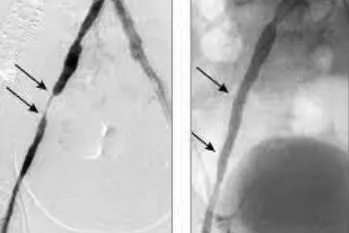

Wiele osób sądzi, że podwyższony cholesterol to nic takiego, w końcu wiele osób taki ma. Wszystkie te osoby pragnę uświadomić, że taka sytuacja stopniowo doprowadza do upośledzonej przepustowości naczyń, a w konsekwencji do poważnych kłopotów zdrowotnych. Do tego dochodzą często bóle klatki piersiowej, szybka męczliwość po znikomym wysiłku, drętwienie rąk i nóg, pieczenie, obrzęki, zasinienie i „marmurkowa” skóra, a w najgorszych przypadkach nawet niewydolność narządów lub procesy martwicze. Wysoki cholesterol wymaga natychmiastowej reakcji.

Przywrócenie prawidłowego profilu cukrowo-tłuszczowego organizmu jest niezwykle istotne, ale to nie wszystko. Cariovico posiada zdolność rozmiękczania, rozluźniania i – ostatecznie – stopniowego rozpuszczania nagromadzonych latami groźnych złogów w naczyniach krwionośnych. Są one w bezpieczny sposób wypłukiwane z organizmu.

Cariovico działa wielopłaszczyznowo. Nie tylko przywraca ciału jego właściwą biochemiczną równowagę i działa udrażniająco na zblokowane lipidami naczynia tętnicze. Ponadto uelastycznia i wzmacnia delikatne tkanki naczyń krwionośnych, poprawiając ich kondycję i zapobiegając obrzękom.

Za sprawą starannie wyselekcjonowanych, maksymalnie stężonych składników, ścianki naczyń krwionośnych zostają oczyszczone ze złogów nawet w 91%, a tlen i substancje odżywcze mogą swobodnie płynąć do tkanek. Prawidłowe krążenie krwi i właściwa praca układu naczyniowo-sercowego to klucz do długiego, zdrowego życia i świetnej kondycji.